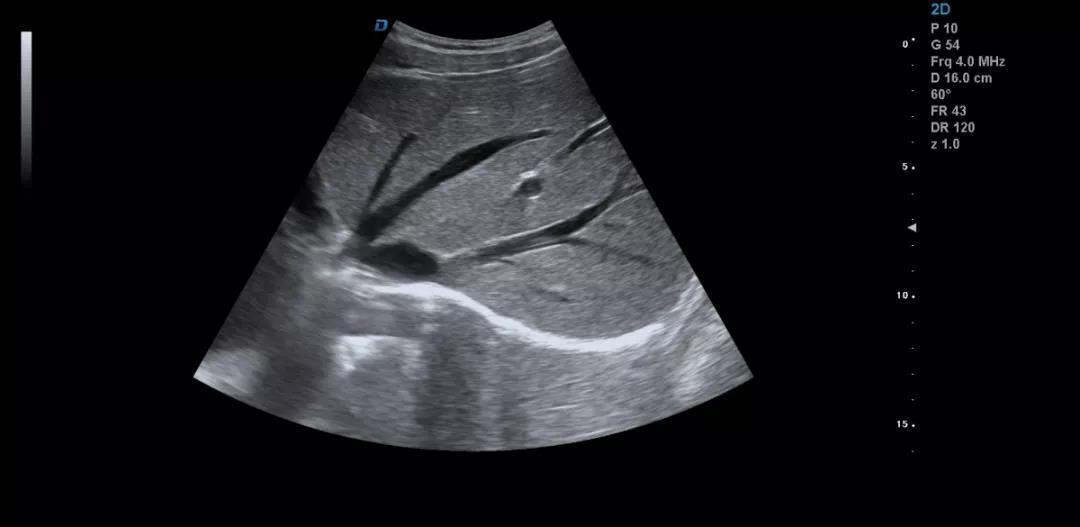

眾所周知,肝臟有很多檢查死角,成為超聲檢查的盲區(qū),如肺和骨所掩蓋處,肝右前上段及右后上段的膈頂部,左外葉外側(cè)角區(qū),沿肝臟表面的肋骨下區(qū)等等部位,只有極其細致的檢查配上精巧的手法才能盡可能的顯示清楚這些部位。

如果我們能夠細致的檢查每個病人,所謂的肝臟死角能夠盡可能的探測到,肝臟的死角其實只有膈頂部,其他的部位如果能細致檢查都可以探測到。

肝臟膈頂部掃查體會:

1)一般是讓患者深吸氣,讓肝臟下移,然后探頭盡量上翹;

2)當然很多患者因肥胖或肺氣的干擾會顯示更差,這時我就讓患者深呼氣,把氣全部吐干凈,然后屏氣掃查;

3)還有就是不要沿著肋間隙掃查,而是和肋間隙成一定的角度緩慢向右上方腋前線掃查;

4)在平臥位掃查時,在橫切腎臟時探頭盡量上翹,甚至與腹壁平行,當然在右側(cè)肋緣下也行;

5)變換體位掃查,肝臟因重力作用產(chǎn)生移位。左側(cè)臥位、右側(cè)臥位、各種斜位、還有站立位等等。

掃查肝臟時要配合患者的呼吸運動,采取你動我靜,你靜我動的掃查方法,并最大限度的側(cè)動探頭,最大角度的顯示肝臟。

發(fā)現(xiàn)肝臟病變時要多切面多角度掃查,可以了解病變的解剖位置并排除假陽性。